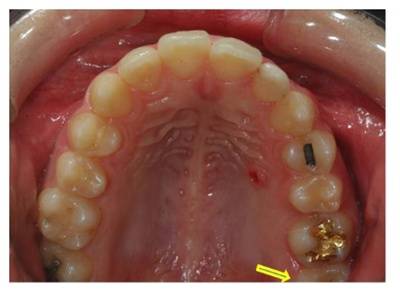

전방 견인장치 제거 8개월 후 재발을 우려하여 유지하고 있던 Mini-implant도 제거하였습니다. #28 (화살표) 치아가 맹출하면서 #27전방에 남아있던 Band space도 소실된 것을 볼 수 있습니다.